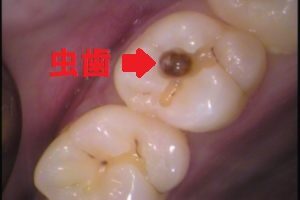

ほとんどの場合、虫歯が原因で根管治療が必要になってきます。

どういうことかというと、虫歯が歯の中に広がって進み、歯の神経まで細菌が侵入してしまうと根管治療が必要になります。

虫歯が神経まで侵入していなければ「虫歯治療」で済むわけですね。